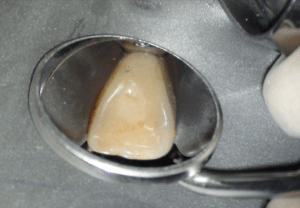

Na anesthesie volgde een flapoperatie om de pocket te openen. Al snel werd een breuk zichtbaar in het element. Maar hoe ver liep de barst door?

Voorzichtig verwijderden we alle granulatieweefsel en spoelden we het schoon. Wat we zagen had ik nog nooit eerder waargenomen. Er zat een min of meer circulaire barst wat eigenlijk een los zittend stukje dentine was.

Na het wegfrezen van het losse stukje vulden we het defect op met composiet. We werken de composiet af met fijne diamantjes en handscalers. Een superscherp geslepen handinstrument kan uitstekend worden gebruikt bij het afwerken van composietvullingen. Wel alleen vlak na het polymeriseren, dan is composiet nog te scalen.

Na polijsten hechtten we de flap en maakten we een afspraak voor een week later.

Toen we de patiënt terug zagen na drie maanden was het aspect van de 11 weer gezond. De pocket was gereduceerd, er was geen pusafvloed meer en het tandvlees zag er gezond uit.

Achteraf analyserend kunnen we stellen dat de situatie niet ideaal is. Er is een composietrestauratie gemaakt in het meest kwetsbare deel van het element en de restauratie ligt gedeeltelijk nog onder de gingiva. We hopen dat het lang goed gaat maar lekkage ligt op de loer natuurlijk en wellicht is het nodig om na een aantal jaren opnieuw een flapje te doen en de restauratie te vernieuwen.